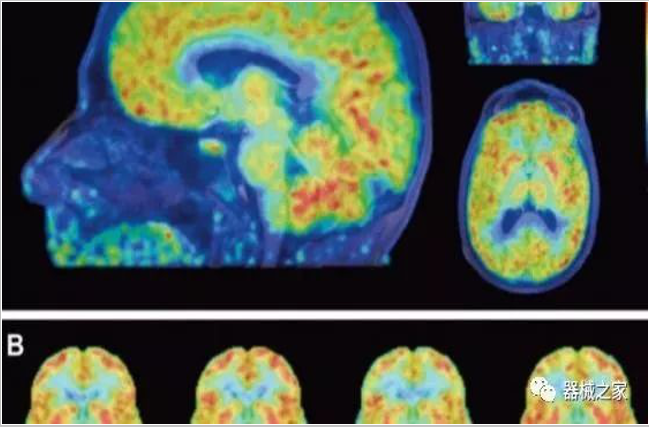

正電子發(fā)射型斷層儀(Positron Emission Tomography, PET)是對(duì)正電子示蹤劑的探測(cè)設(shè)備,具有極高靈敏度和精準(zhǔn)的定量功能。而PET/CT是將PET與CT有機(jī)結(jié)合起來(lái)的融合設(shè)備,已經(jīng)成為腫瘤、神經(jīng)和心血管系統(tǒng)疾病診斷,臨床分期和療效評(píng)估的最佳影像技術(shù)。

PET掃描顯示成年女性大腦比男性年輕三歲!